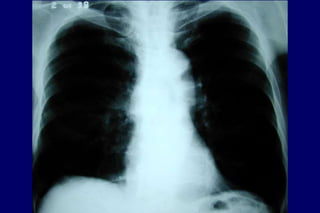

Radiografia

de tórax

Excluir outras

doenças

Bolhas

Hiperinsuflação